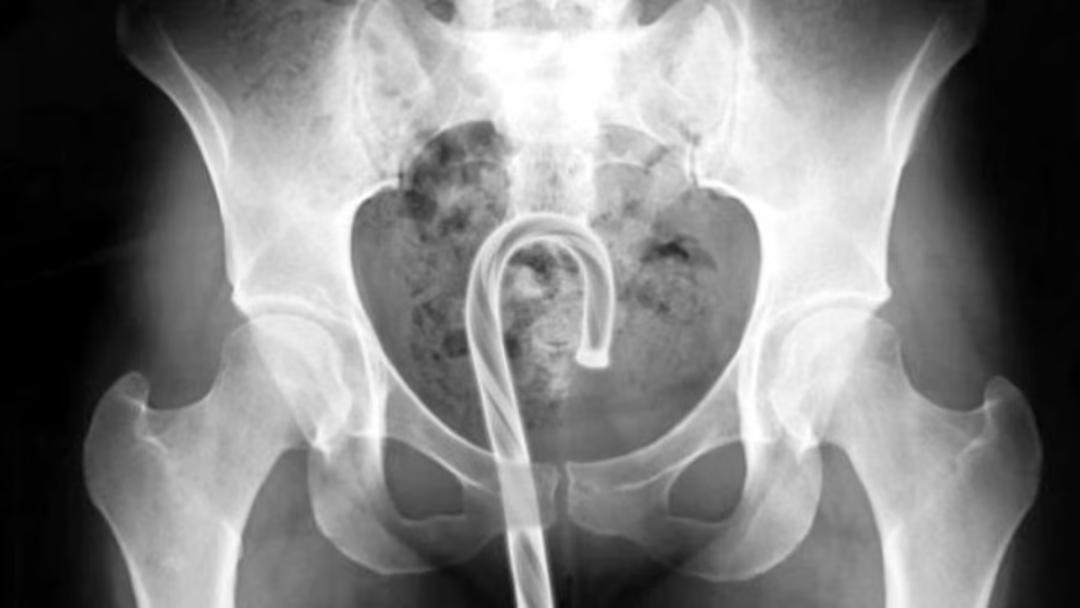

除了以上这些常规病人外,他们这些肛肠科医生还听说,法国那边的一个医院,某年的深夜急诊室里来了一位直肠塞着炮弹的88岁大爷。

专家在看到X光片后也表示,这题有点太超纲了,需要寻求拆弹专家的帮助,并疏散了全院的人员。

最终,在拆弹专家和医护人员的配合下,这枚诞生于第一次世界大战、长约20.8厘米、粗约5厘米的古董炮弹终于被取出来了。